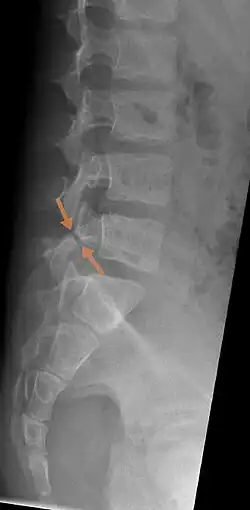

Arrows show break in pars interarticularis at L5. X-Ray of lumbar spine, lateral projection, in an 11-year-old boy

Spondylolysis also known as a pars defect or pars fracture, is a defect or stress fracture in the pars interarticularis of the vertebral arch.[1][2] The vast majority of cases occur in the lower lumbar vertebrae (L5), but spondylolysis may also occur in the cervical vertebrae.[3]